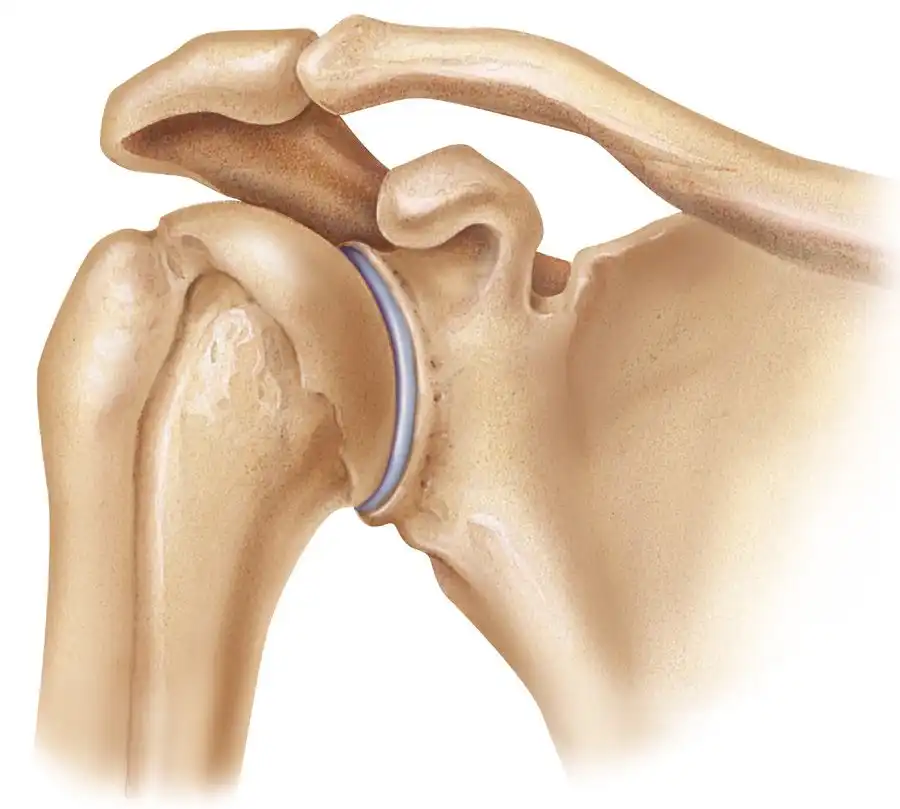

پارگی تاندون روتاتور کاف (Rotator cuff) | علائم، دلایل، روشهای درمان و فیزیوتراپی تخصصی در سال1405 ادامه مطلب »

همهچیز درباره عمل پارگی تاندون شانه در سال 1405 | مراحل جراحی، نکات طلایی و مراقبتهای بعد از عمل ادامه مطلب »

جراحی مفصل شانه در سال 1405 | قیمت، نکات طلایی و راهنمای قدمبهقدم برای بازگشت بدون درد ادامه مطلب »